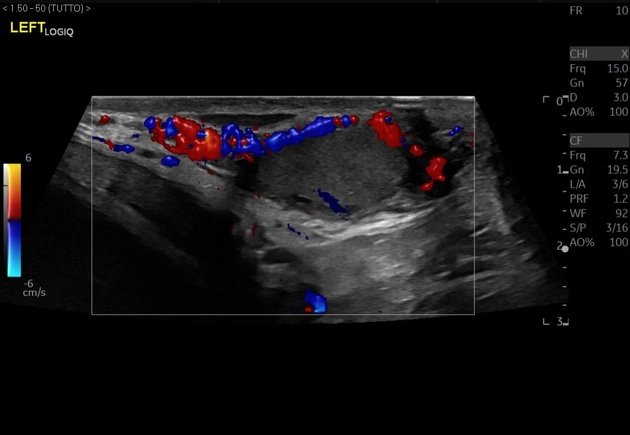

• Bìu và thừng tinh

• Khối u ở bìu